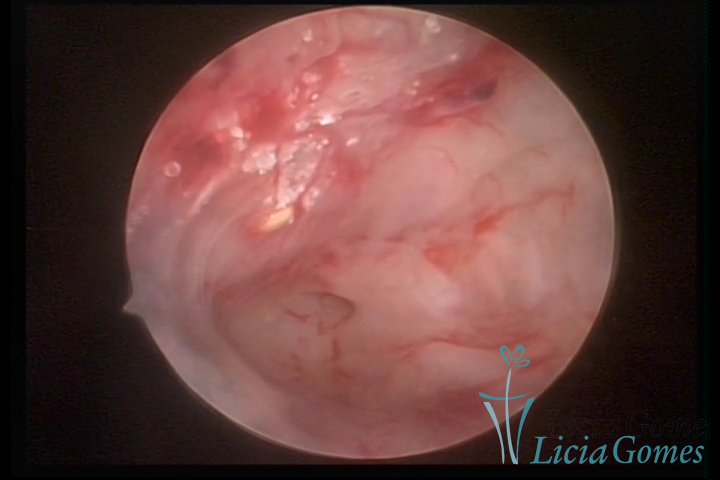

Osseous metaplasia and adenomyosis lesions